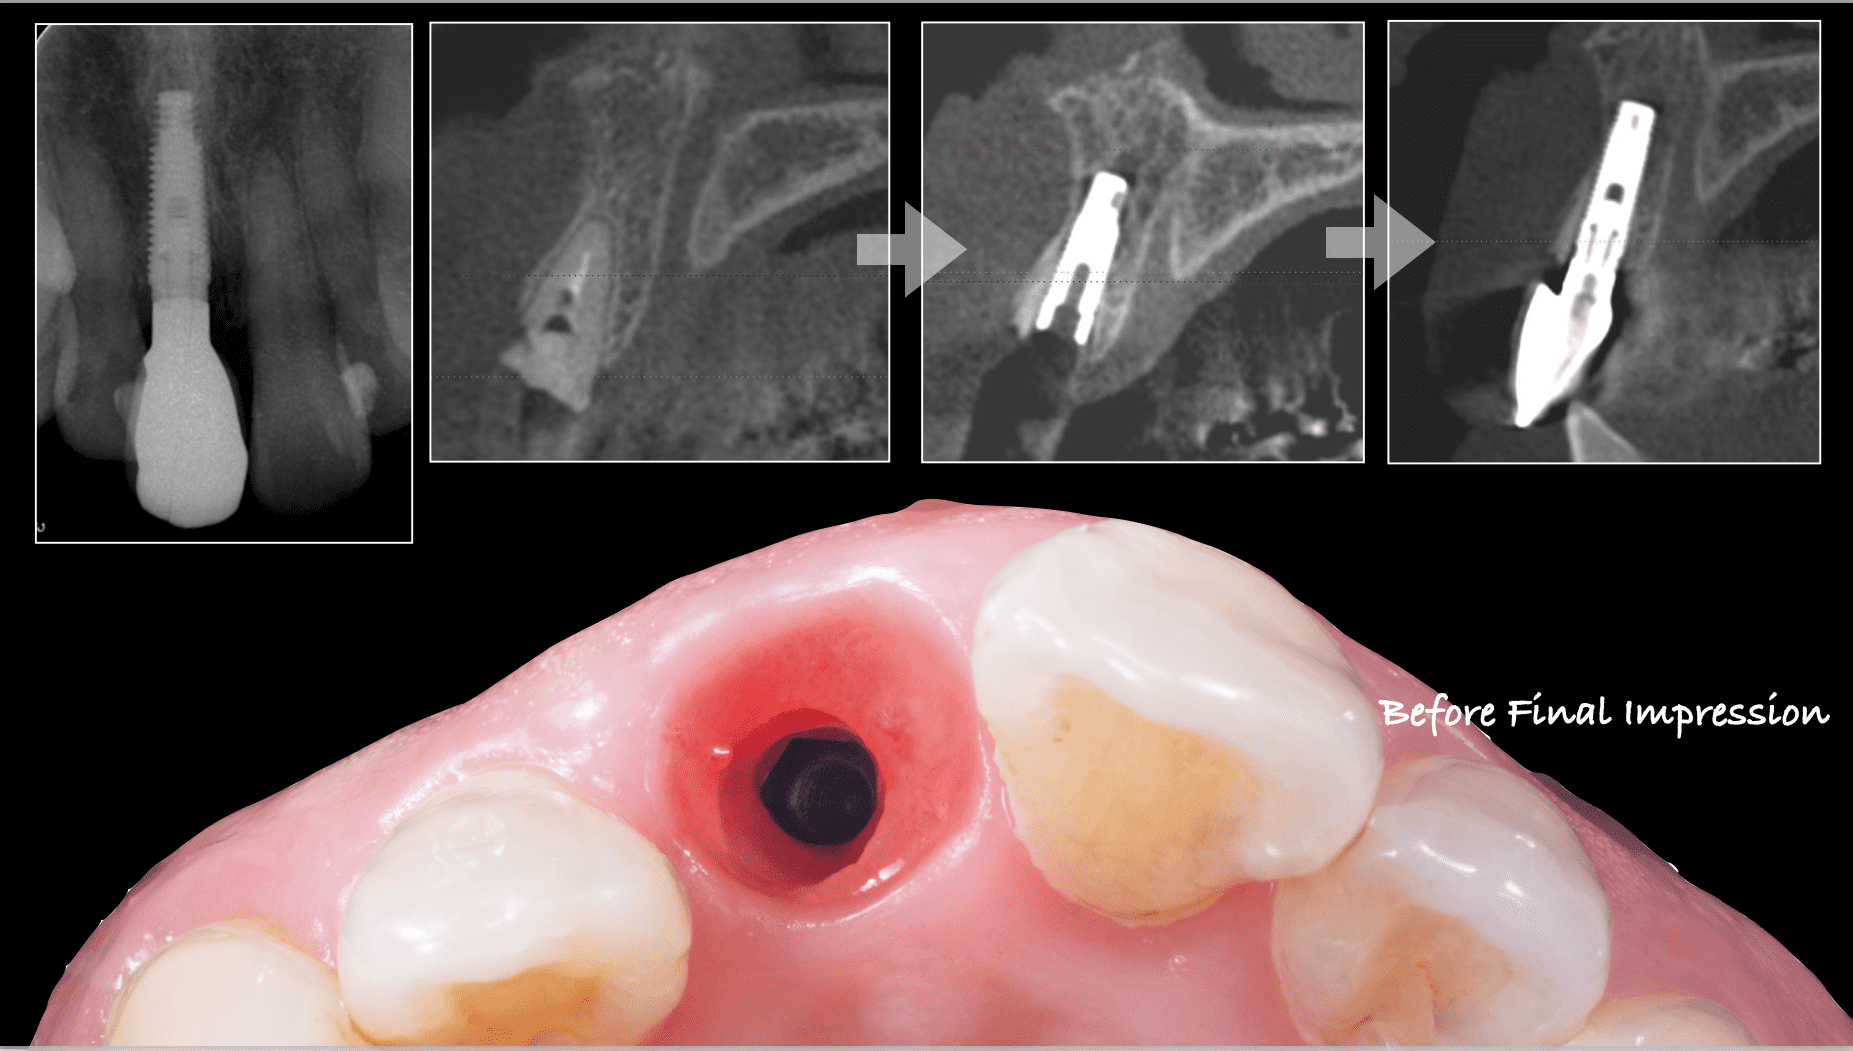

症例紹介29:インプラント治療/前歯_ソケットシール《50代女性》

治療内容:食事中に前歯が破折し、治療を希望し来院。

上顎:折れた歯を見ると、一部被せ物に歯が残っており保存不可能な状態。

上顎:歯には太い土台が入っており、折れて保存不可能な状態

最終補綴

上顎:フルジルコニアスクリューリテイン

リスク:残っている歯の一部を残してインプラントを入れることによって、歯茎が下がるのを抑えることができます。